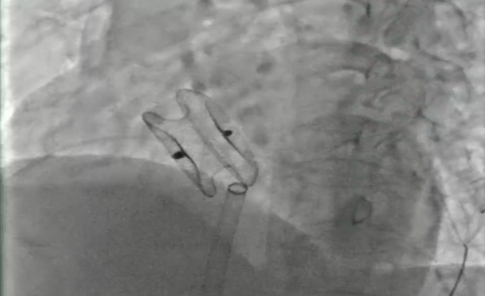

为患者行射频消融治疗

成功封堵

我院心血管内科介入团队经详细评估后,开展了充分的术前讨论,决定为张阿姨行“室上速射频消融手术+房间隔缺损封堵术”的一站式手术。该方案通过介入微创实施,一个小穿刺点伤口完成两个手术,不仅大大减轻分次手术给患者带来的痛苦及经济负担,而且术后恢复快。最终手术成功实施,术后第二天患者即可下床活动。